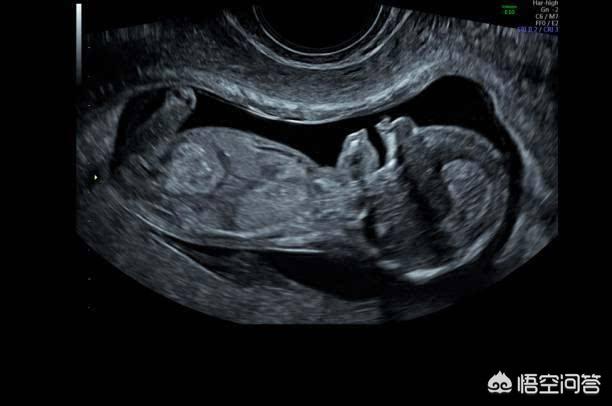

Beim B-Ultraschall werden im Allgemeinen die Entwicklung des Fötus und die Lage der Plazenta untersucht, selten geht es um fötale Erkrankungen. Nur beim 4D-Ultraschall werden fötale Fehlbildungen festgestellt, so dass es sich bei Ihrer Frage um den 4D-Ultraschall und nicht um den B-Ultraschall handeln sollte.

Mit dem Ultraschall kann überprüft werden, ob die Lage des Fötus normal ist, ob das Fruchtwasservolumen abnormal ist, ob die Nabelschnur des Fötus um den Hals gewickelt ist, ob die Entwicklung des Fötus verzögert ist und ob die Plazenta niedrig ist.

Die Ultraschalluntersuchung während der Schwangerschaft kann vor allem das Wachstum und die Entwicklung des Fötus, seine physiologische Aktivität, die Menge des Fruchtwassers und den Zustand der Plazenta feststellen.

Die Ultraschalluntersuchung dient der Erkennung von Problemen mit der Plazenta, dem Fötus, dem Fruchtwasser und der Nabelschnur und ist ein wichtiger Bestandteil der schwangerschaftsbegleitenden Vorsorgeuntersuchung.